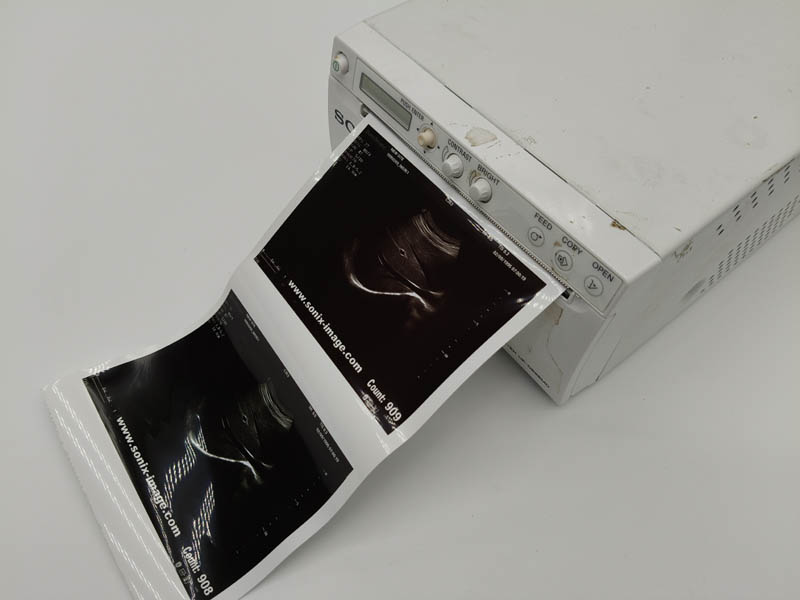

- Printing Effect for Our Type V video p